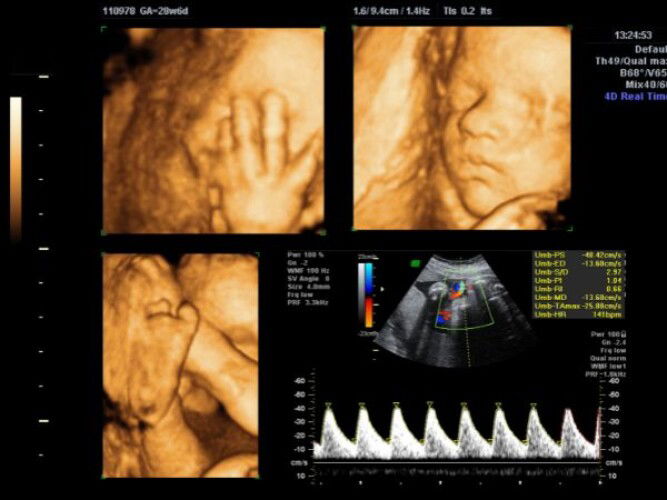

When is the best time to have a 4D ultrasound in pregnancy?